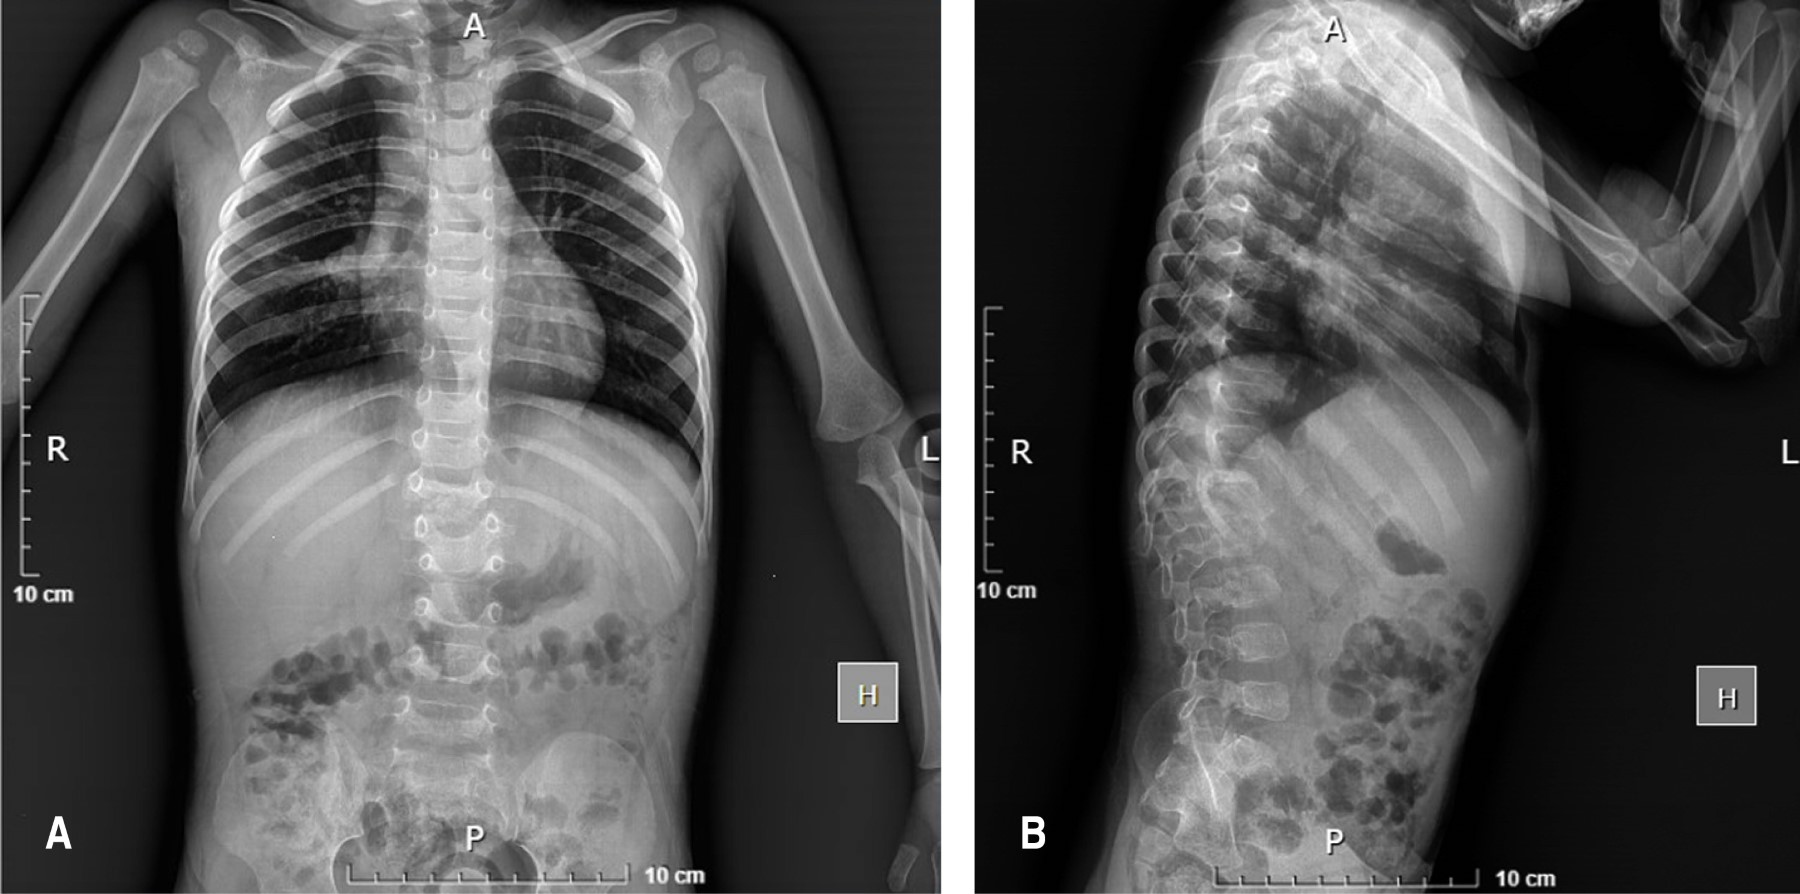

Se reportó una pérdida de peso de 2 kg en un corto periodo de tiempo, lo cual generó preocupación por un proceso infeccioso o inflamatorio subyacente. Se realiza estudio de resonancia magnética nuclear de columna dorsolumbar contrastada (Figura 2), en la cual se muestra síndrome de destrucción vertebral con fractura patológica de las vértebras T12 y L1, erosión en cuerpo vertebral de L1, así como presencia de masa de tejidos blandos hiperintensa con involucro de cuerpo anterior y posterior que formaba una colección (37 × 50 × 47 mm) de aspecto subdural, con contacto de elementos neurales y, al administrar contraste, con realce de la pared con un centro hipointenso. También se solicitó una tomografía axial computarizada de columna dorsolumbar, donde se encontró consolidación pulmonar en la región parahiliar derecha (2.6 × 2.1 cm), junto con adenomegalias cervicales y mediastinales.

Ante la pobre mejoría clínica con el tratamiento conservador durante dos meses, se realizan rayos X (Figura 3) y resonancia magnética nuclear de control (Figura 4), donde se identificó permanencia del colapso vertebral, compresión de elementos neurales y extensión de la colección hacia la región prevertebral y los músculos iliopsoas bilaterales, con cambios en la intensidad de señal a nivel medular sugestivos de mielopatía en el área afectada. Se realiza intervención quirúrgica mediante instrumentación posterior toracolumbar de T12 a L3, hemilaminectomía izquierda en T12-L1 y drenaje de abscesos con obtención de 3 cc de líquido de aspecto purulento en el espacio T12-L1 y alrededor de 8 cc en la región del psoas derecho (Figura 5 y 6).